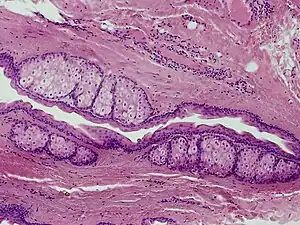

The cysts are mostly small (2–20 mm) but they may be several centimetres in diameter. They tend to be soft to firm semi-translucent bumps, and contain an oily, yellow liquid. Sometimes a small central punctum can be identified and they may contain one or more hairs (eruptive vellus hair cysts). They may become inflamed and heal with scarring, like acne nodules (see nodulocystic acne and hidradenitis suppurativa).

Steatocystomas are thought to come from an abnormal lining of the passageway to the oil glands (sebaceous duct).